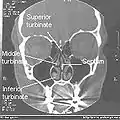

Nasal conchae: Blocked/free

Normal Nose CT Front cross section

Coronal section of nasal cavities